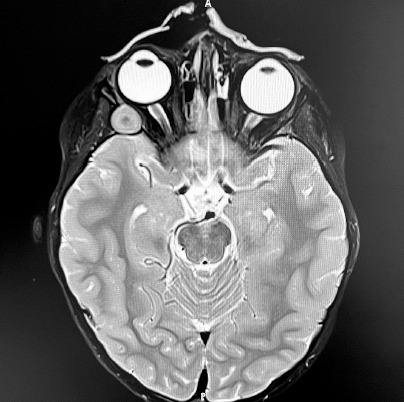

For further evaluation, the patient was referred to the Department of Pediatric Hematology and Oncology at Karol Jonscher Clinical Hospital in Poznan with a diagnosis of iritis and a suspected orbital tumor . A contrast-enhanced magnetic resonance imaging (MRI) scan of the craniofacial region was performed, revealing a well-circumscribed, slightly heterogeneous tumor mass measuring 12 × 11 × 15 mm within the right orbital boundaries, in the area of the greater wing of the sphenoid bone. The lesion demonstrated no post-contrast enhancement and showed no diffusion restriction on DWI/ADC sequences (Figure 3). Orbital computed tomography (CT) revealed bone thinning likely caused by the tumor mass, along with segmental disruption of the orbital walls adjacent to the lesion (Figure 4). The radiological findings raised suspicion of malignancy, leading to a planned biopsy. However, intraoperatively, the tumor’s well-defined margins prompted a decision to proceed with complete tumor resection with the capsule. The subsequent histopathology examination confirmed the diagnosis of DC. Symptomatic treatment for right eye uveitis was continued.